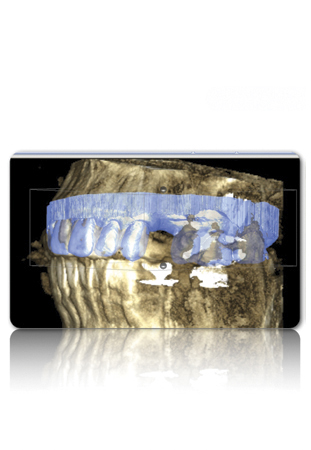

Figure 3 Examples of using digital workflow to import restoration data and plan implant treatment: the intraoral scan (IOS) data pinned to the CBCT (Fig 3); the designed ideal restoration being imported into the CBCT (Fig 4); the implant placed with the restoration and IOS toggled off (Fig 5).

Figure 3

Figure 4 Examples of using digital workflow to import restoration data and plan implant treatment: the intraoral scan (IOS) data pinned to the CBCT (Fig 3); the designed ideal restoration being imported into the CBCT (Fig 4); the implant placed with the restoration and IOS toggled off (Fig 5).

Figure 4

Figure 5 Examples of using digital workflow to import restoration data and plan implant treatment: the intraoral scan (IOS) data pinned to the CBCT (Fig 3); the designed ideal restoration being imported into the CBCT (Fig 4); the implant placed with the restoration and IOS toggled off (Fig 5).

Figure 5

Although workflows can vary, in many implant cases, typically a CBCT scan of the area of concern is made. Then, with an intraoral scan or digital version of a model or impression, the practitioner begins working with the design software of the particular intraoral scan or CBCT system being used (Figure 3 through Figure 5). The edentulous area or area where teeth are to be extracted can then be thoroughly evaluated. Ideal restorations can then be previsualized or treatment planned from both an esthetic and functional standpoint. Once this is done, the intraoral information is pinned or overlaid onto the CBCT scan. The restoration(s) can then be imported into the software system, toggled on or off—ie, shown or not—and the underlying bone evaluated.3